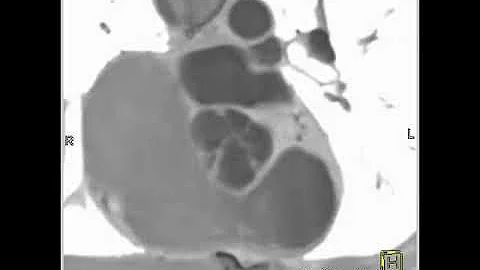

4-d Mri Of Bicuspid Aortic Valve Disease

Michael Markl, PhD, director of Cardiovascular Magnetic Resonance Imaging (MRI) Research Operations, is using 4D flow ...